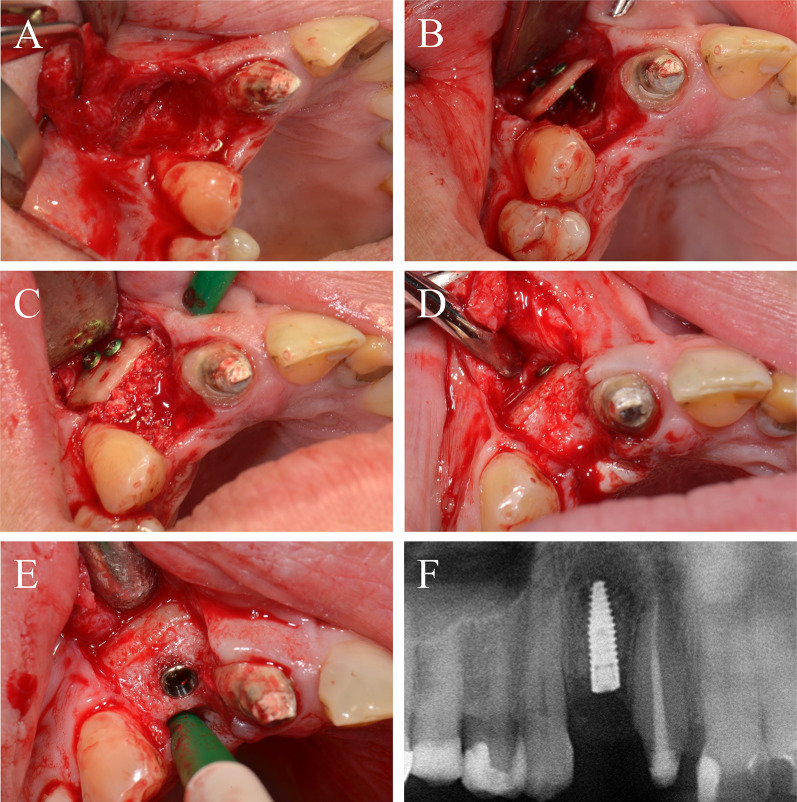

A 25-year-old patient presented himself after multiple tooth loss of the right maxilla and an extended horizontal tub-shaped and partially vertical bone atrophy and a wish for an implant-borne prosthetic restoration. In the past, alveolar ridge augmentation has been performed using autogenous bone block from the mandibular angle with a failure of the transplant after a few weeks because of transplant infection. Therefore, in accordance to patient’s wishes, the current treatment plan included a re-augmentation using CP. After palatinal-shifted crestal incision, a full-thickness flap was raised with marginal alleviations. After preparation of the recipient site by using a sharp raspatorium, the defect size was measured and CP was extra orally prepared, placed and fixed by two adjusting screws (each 1.5 × 10 mm) (Fig. 6A). The space between the CP and the local bone was filled with allogeneic granules and the augmented area was covered by a porcine pericardium collagen membrane (Fig. 6B). After 6 weeks, an asymptomatic and painless dehiscence defect was found (Fig. 6C). Extensive mouth hygiene was performed with mouth rinsing solutions (0.2% chlorhexidine), up to three times a day for 6 weeks. After 3 months, CBCT scan was performed to analyze the current bony situation and to plan implant placement showing sufficient horizontal bone volume (Fig. 6D). After 4 months, the augmented area was revisited. The inserted CP showed a plate fracture alongside the screw line (Fig. 6E). The upper part of the broken CP was removed after removal of the adjusting screws. The local bone was sufficient for implant placement and three implants (BLT, 3.3/4.1 × 10 mm, Straumann) were placed (Fig. 6F). Within the follow-up of 40 months, the case remained stable without complications.

Fig. 6.

Alveolar ridge augmentation of the maxilla with wound dehiscence. A The intraoperative baseline showed an extended horizontal alveolar ridge atrophy. An allogeneic cortical bone plate was fixed laterally to the defect by two adjusting screws. B The space between the allogeneic cortical bone plate and the local alveolar ridge bone was filled with spongious allogeneic granules and the area was covered by a porcine pericardial matrix. C After a few weeks, a dehiscence defect with an exposure of the allogeneic CP was found. D Surgical re-evaluation demonstrated a plate fracture along the screw holes (white arrows). E CBCT scan demonstrated a sufficient bone volume for implant placement. F X-ray demonstrating the inserted implants